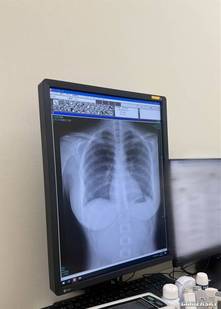

近期,她一个别出心裁的举动再次吸引了众人目光:在社交平台上公开了自己的肺部X光片。这张影像不仅展现了其健康状况,更因为日本写真偶像极少公开此类个人医疗信息而引发热议。

为什么写真偶像直接公开X光片的情况非常少见?一方面涉及医疗法规,另一方面,专业人士也能通过此类影像观察胸部构造,从而间接印证其是否为纯天然、未经整形。

有人则专业点评其肺部“这张胸部正位X光片显示肺部状况极佳。双肺野清晰,未见浸润、结节或胸腔积水。心脏轮廓正常,胸廓骨骼未见骨折或异常。”,